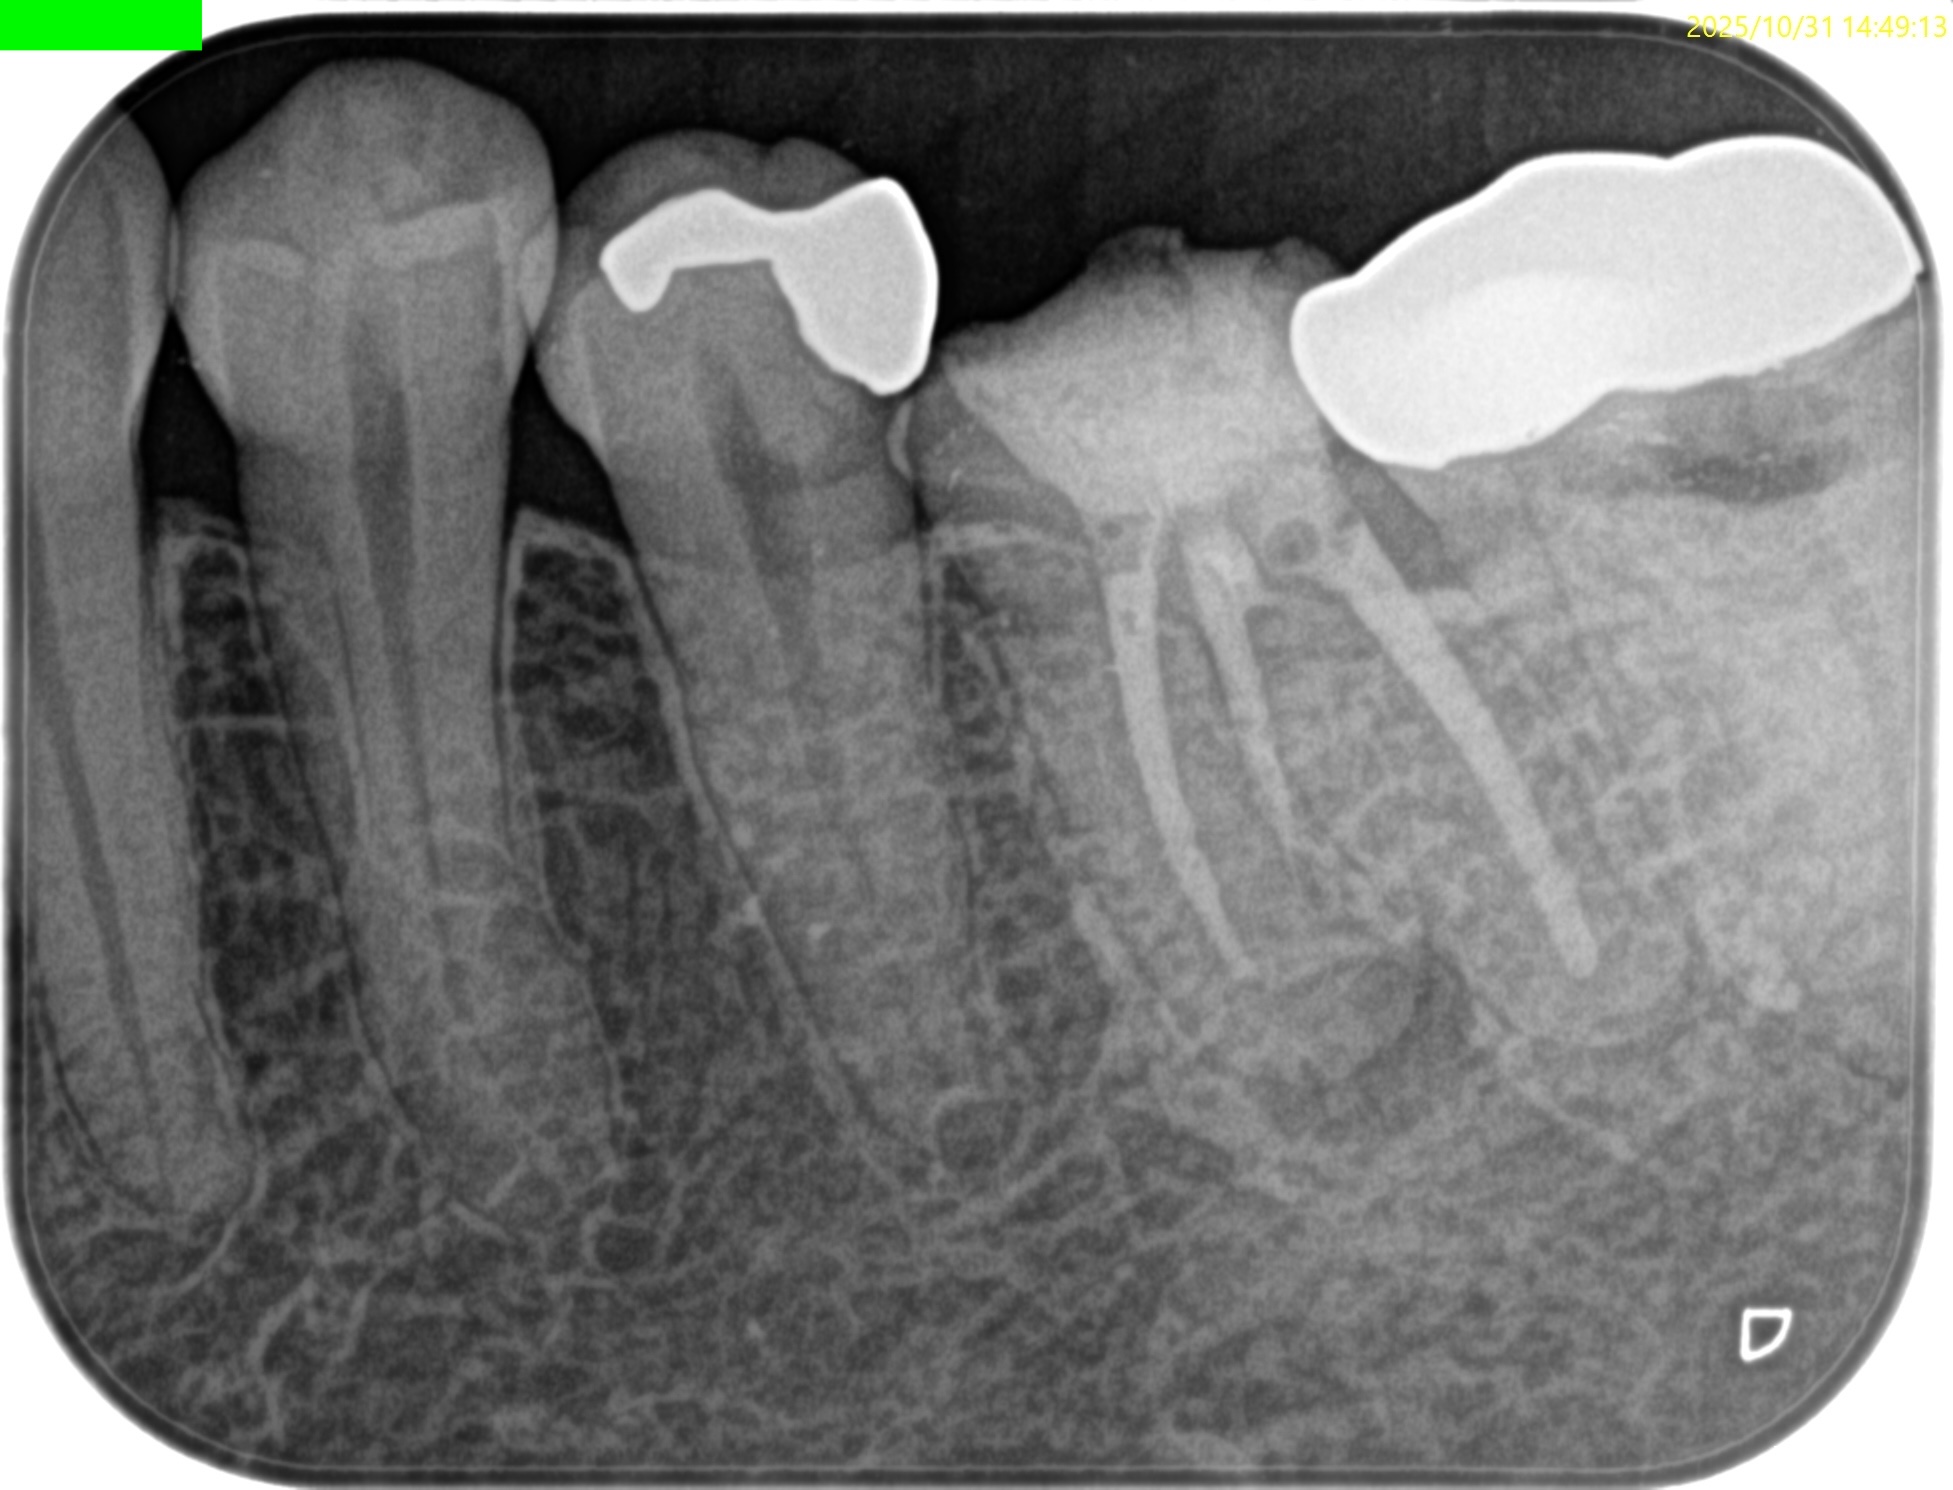

PA(2025.10.31)

PAでは上記の私の謎は解明できない。

#19の近心根には根尖病変は見えるが…

圧痛が強いのは#18近心だ。

意味がわからない。